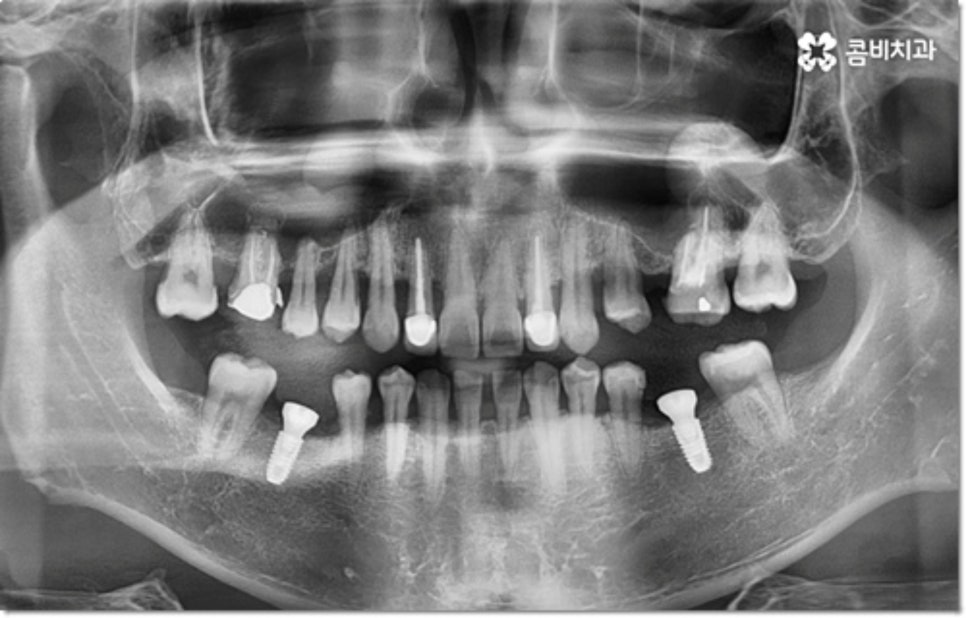

사진에서 볼 수 있는 사례는 아랫니가 크게 부러져서 빠졌을 때 아랫니임플란트 시술을 통해 수복을 해 준 거예요. 이때 빠른 일상 복귀를 원하는 만큼 기간이 얼마나 오래 걸리는가 하는 것은 임플란트 시술을 받으시는 분들의 가장 주된 관심사 중 하나라고 할 수 있는데요.

임플란트 시술 기간은 환자분들의 상황에 따라 달라지는 것이지만 보통 빠르면 36개월, 뼈이식이나 상악동 거상술과 같은 선처치가 필요한 경우 또는 회복 기간이 생각보다 오래 걸리는 경우에는 8개월1년 넘게 까지도 걸릴 수 있습니다. 혹시 모를 부작용으로 재시술을 받게 되는 경우도 있기 때문에 치과를 선택하실 때 말씀드린 의료진의 숙련도 외에도 여러 가지 사항들을 꼼꼼하게 따져보실 필요가 있어요. 3D CT 와 같은 정밀 장비로 환자분들의 잇몸 상황 또는 교합 등을 세밀하게 살펴보고 그에 맞춰 무리하지 않게 임플란트 식립을 진행하는 치과에서 검진부터 사후관리까지 체계적으로 케어받는 것이 중요한 거예요.

하지만 통상적으로는 심미적으로 보다 자연스러워 보이는가 하는 부분이 시술 후 만족도와 직결되는 경우가 많아 앞니가 어금니보다 더 까다롭고, 윗니가 아랫니임플란트 시술보다 어렵다고 볼 수 있습니다. 빛이 어느 정도 투과되어 보이는 자연 치아 본연의 색상을 잘 살리고 잇몸 라인이 어색해지지 않게 신경써서 식립을 진행해야 하는 앞니와 윗니 부위 시술이 어금니, 아랫니임플란트 시술 보다 숙련된 의료진의 경험이 중요하다고 볼 수 있습니다.